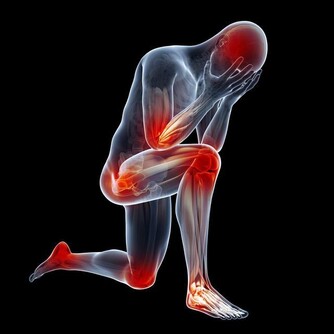

說到肛門,可能有些人覺得很害羞,一些關於肛門的事情也羞於啟齒,它也是我們的身體部位中最令人嫌棄的一個部位,同時也是我們身體排出垃圾的最後一步。

但其實我們的身上沒有一個部位是沒有用的,首先肛門的作用就有排氣,在日常生活中,無論是吃飯還是說話時,都會導致一些氣體進入到食道中,這時人體就會感到胃脹不舒服的感覺,要想排出就要通過肛門。

其次,排便可以說是我們每天都要做的事了,雖然很麻煩但是幾天不排我們還會很難受,我們體內的垃圾和毒素都要通過肛門排出,如果這些東西不排出就會導致肥胖,小肚子變大,甚至腸胃疾病。

最後肛門也有這保護腸胃的功能,很多人可能有些納悶肛門跟腸胃有什麼關係,其實肛門和我們的腸胃是連著的,也在為我們的腸胃阻擋一些外來細菌,因此如果肛門不及時清潔產生了細菌,久而久之就會導致細菌進入到腸道內部,引起腸道疾病。